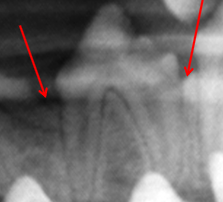

Alveolar Crest

ID

Lamina Dura

Periodontal Membrane